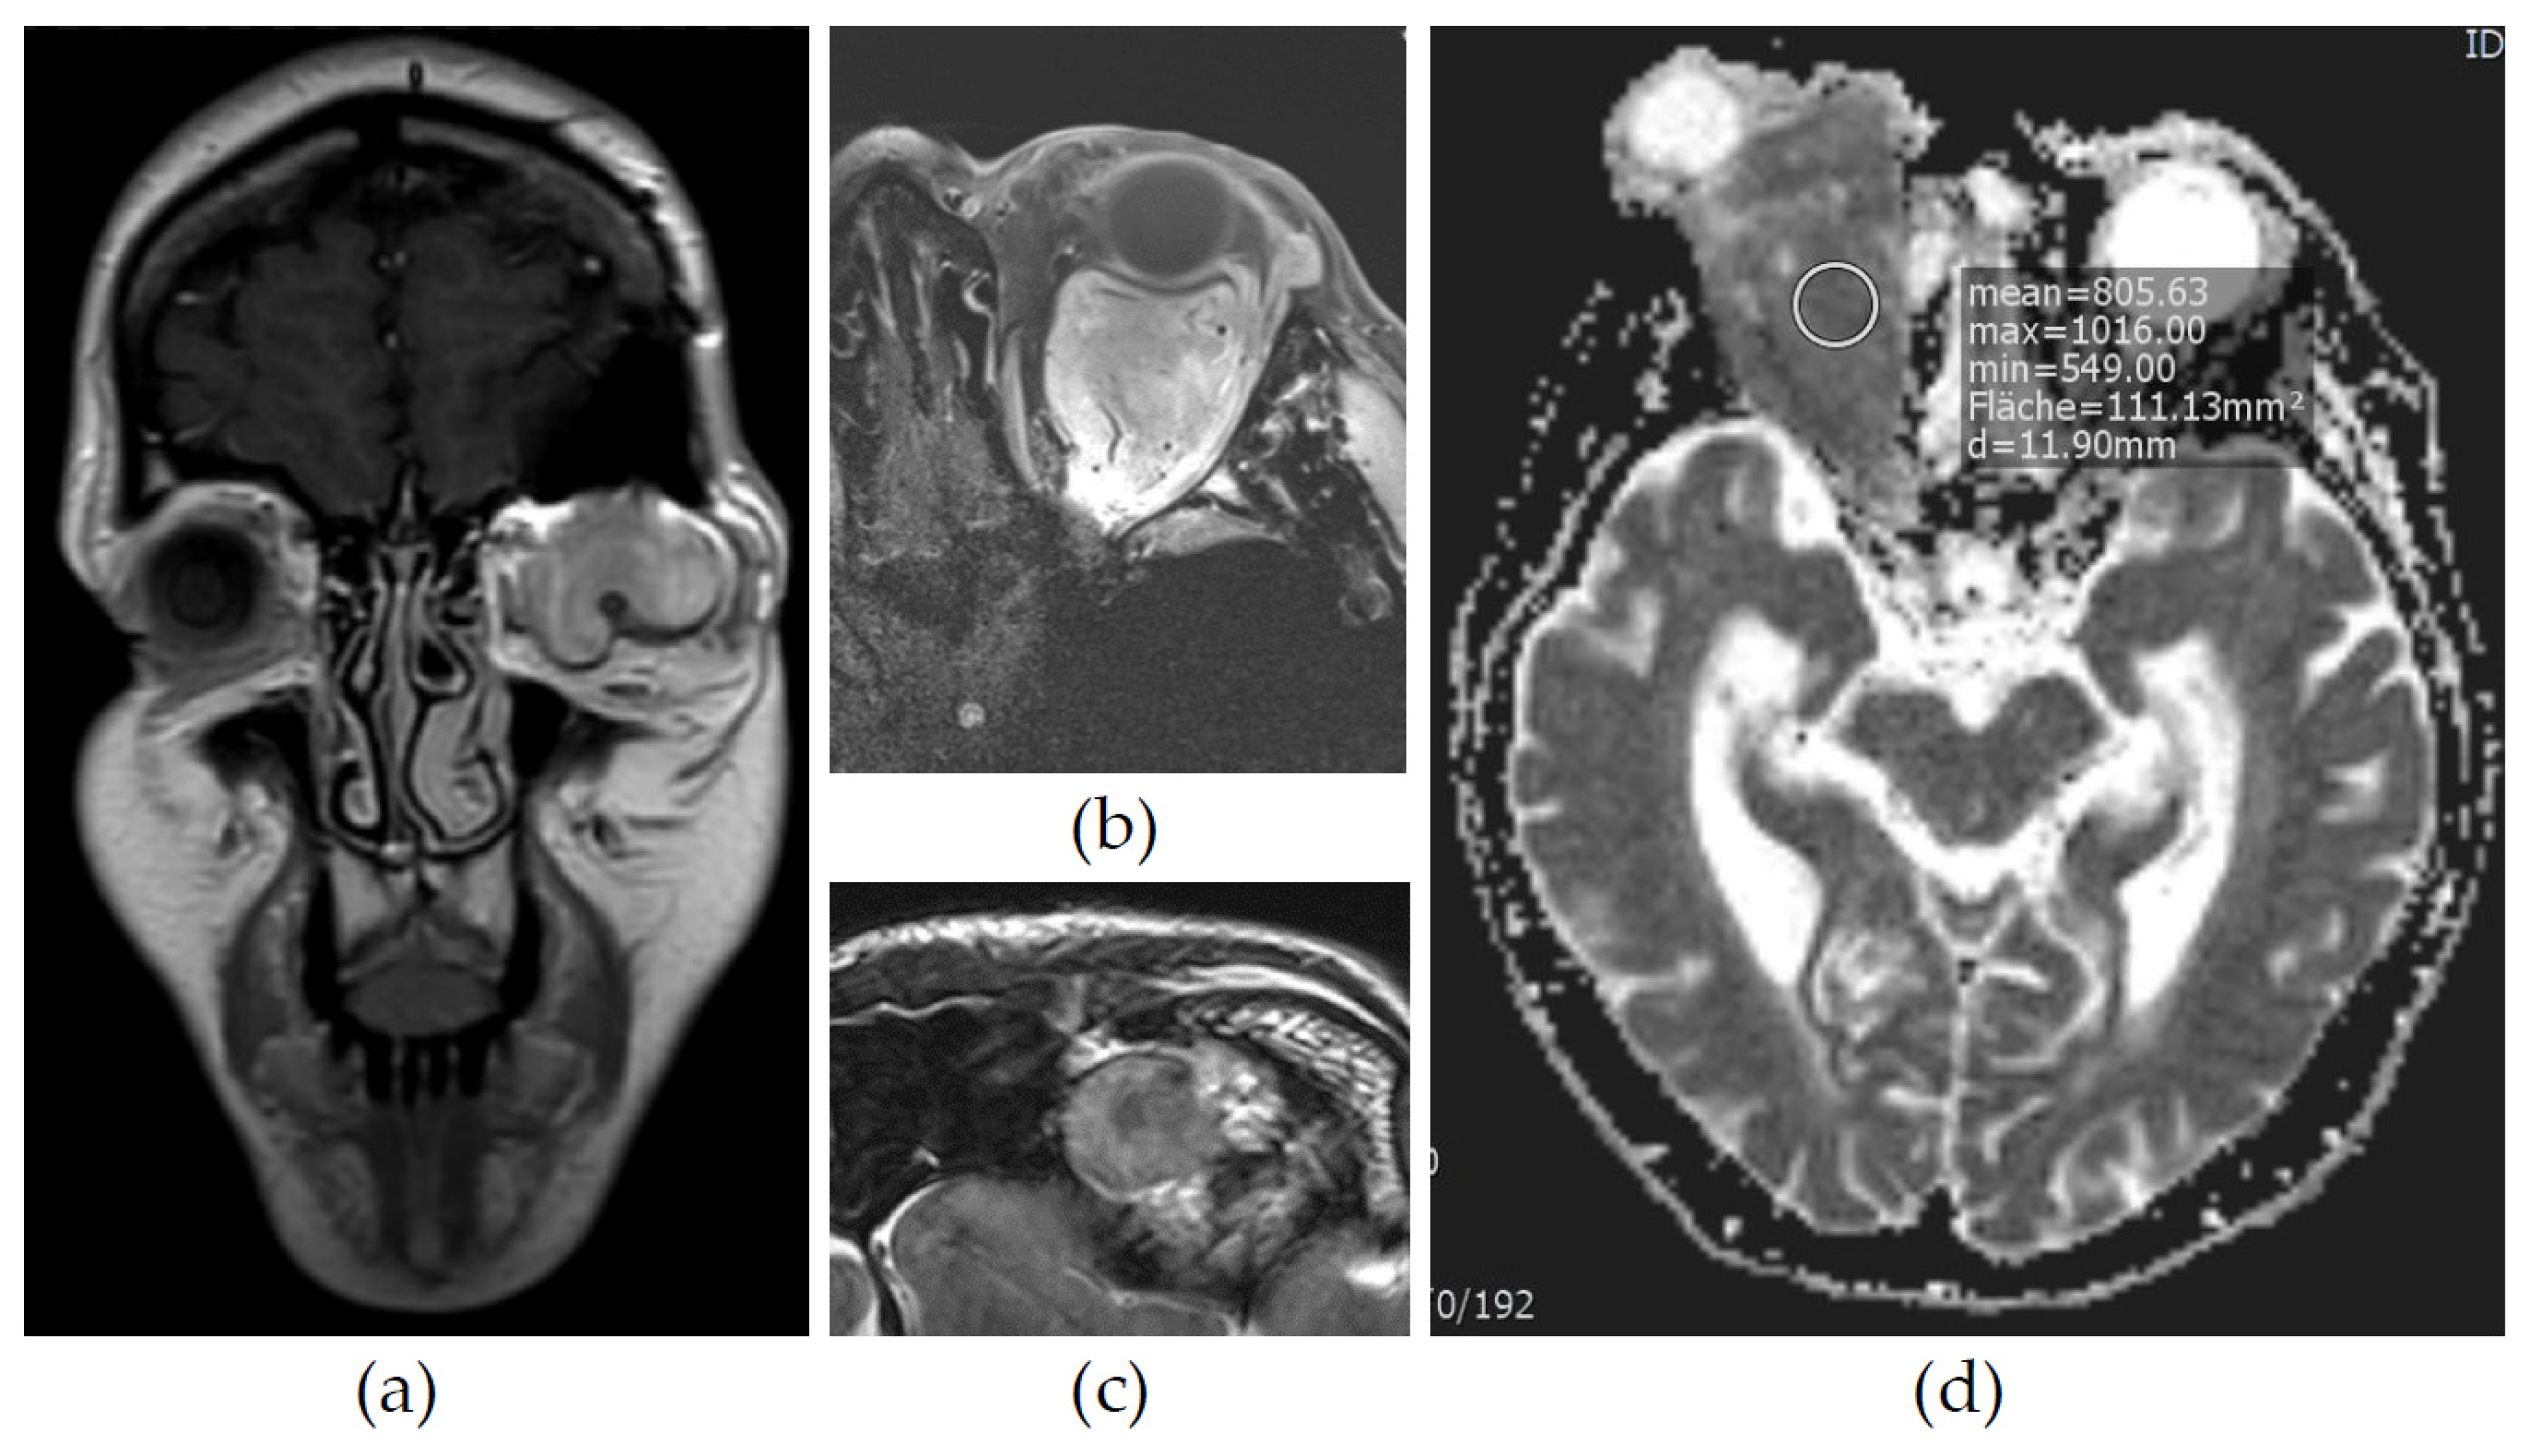

3.2. Imaging

| 9 | Hyperdense | Hypointense | Intermediate | − | Reduction | Inhomogeneous | No vessels, well circumscribed, inhomogeneous, no compression |